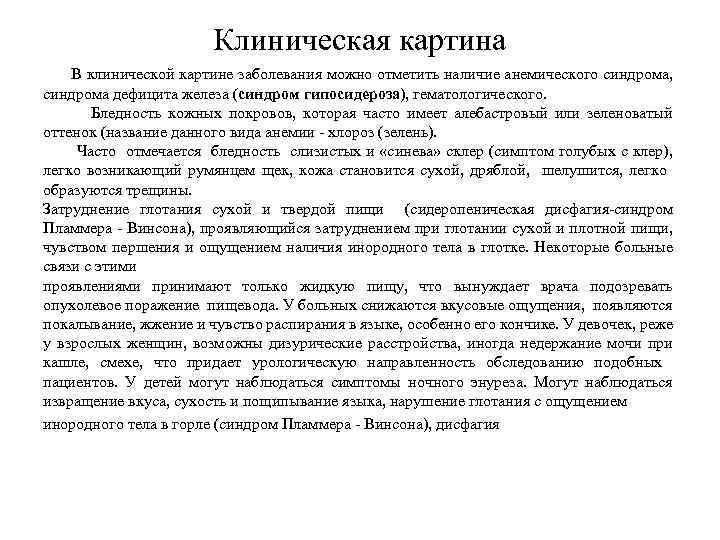

Клиническая картина В клинической картине заболевания можно отметить наличие анемического синдрома, синдрома дефицита железа (синдром гипосидероза), гематологического. Бледность кожных покровов, которая часто имеет алебастровый или зеленоватый оттенок (название данного вида анемии - хлороз (зелень). Часто отмечается бледность слизистых и «синева» склер (симптом голубых с клер), легко возникающий румянцем щек, кожа становится сухой, дряблой, шелушится, легко образуются трещины. Затруднение глотания сухой и твердой пищи (сидеропеническая дисфагия-синдром Пламмера - Винсона), проявляющийся затруднением при глотании сухой и плотной пищи, чувством першения и ощущением наличия инородного тела в глотке. Некоторые больные связи с этими проявлениями принимают только жидкую пищу, что вынуждает врача подозревать опухолевое поражение пищевода. У больных снижаются вкусовые ощущения, появляются покалывание, жжение и чувство распирания в языке, особенно его кончике. У девочек, реже у взрослых женщин, возможны дизурические расстройства, иногда недержание мочи при кашле, смехе, что придает урологическую направленность обследованию подобных пациентов. У детей могут наблюдаться симптомы ночного энуреза. Могут наблюдаться извращение вкуса, сухость и пощипывание языка, нарушение глотания с ощущением инородного тела в горле (синдром Пламмера - Винсона), дисфагия